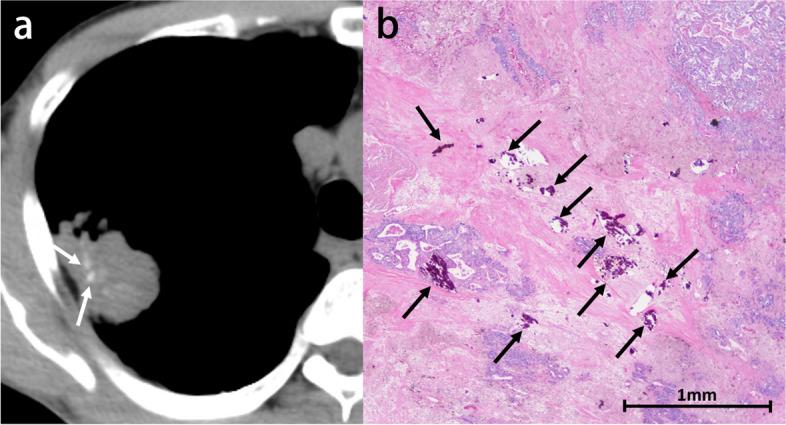

CT上高衰减肺部异常的逐步诊断算法

Stepwise diagnostic algorithm for high-attenuation pulmonary abnormalities on CT.

High-attenuation pulmonary abnormalities are commonly seen on CT. These findings are increasingly encountered with the growing number of CT examinations and the wide availability of thin-slice images. The abnormalities include benign lesions, such as infectious granulomatous diseases and metabolic diseases, and malignant tumors, such as lung cancers and metastatic tumors. Due to the wide spectrum of diseases, the proper diagnosis of high-attenuation abnormalities can be challenging. The assessment of these abnormal findings requires scrutiny, and the treatment is imperative. Our proposed stepwise diagnostic algorithm consists of five steps. Step 1: Establish the presence or absence of metallic artifacts. Step 2: Identify associated nodular or mass-like soft tissue components. Step 3: Establish the presence of solitary or multiple lesions if identified in Step 2. Step 4: Ascertain the predominant distribution in the upper or lower lungs if not identified in Step 2. Step 5: Identify the morphological pattern, such as linear, consolidation, nodular, or micronodular if not identified in Step 4. These five steps to diagnosing high-attenuation abnormalities subdivide the lesions into nine categories. This stepwise radiologic diagnostic approach could help to narrow the differential diagnosis for various pulmonary high-attenuation abnormalities and to achieve a precise diagnosis.Critical relevance statement Our proposed stepwise diagnostic algorithm for high-attenuation pulmonary abnormalities may help to recognize a variety of those high-attenuation findings, to determine whether the associated diseases require further investigation, and to guide appropriate patient management. Key points • To provide a stepwise diagnostic approach to high-attenuation pulmonary abnormalities.• To familiarize radiologists with the varying cause of high-attenuation pulmonary abnormalities.• To recognize which high-attenuation abnormalities require scrutiny and prompt treatment.

高衰减肺部异常在CT上很常见。随着CT检查数量的增加和薄层图像的广泛应用,这些发现越来越多地被遇到。这些异常包括良性病变,如感染性肉芽肿疾病和代谢性疾病,以及恶性肿瘤,如肺癌和转移性肿瘤。由于疾病谱广泛,对高衰减异常进行正确诊断可能具有挑战性。对这些异常发现的评估需要仔细审查,且治疗势在必行。我们提出的逐步诊断算法包括五个步骤。步骤1:确定是否存在金属伪影。步骤2:识别相关的结节状或肿块样软组织成分。步骤3:如果在步骤2中识别出病变,确定是单发还是多发。步骤4:如果在步骤2中未识别出病变,确定在上肺还是下肺的主要分布。步骤5:如果在步骤4中未识别出病变,识别形态模式,如线状、实变、结节状或微结节状。这五个诊断高衰减异常的步骤将病变细分为九类。这种逐步的放射学诊断方法有助于缩小各种肺部高衰减异常的鉴别诊断范围,并实现精确诊断。关键相关性声明我们提出的高衰减肺部异常逐步诊断算法可能有助于识别各种高衰减表现,确定相关疾病是否需要进一步检查,并指导适当的患者管理。要点• 为高衰减肺部异常提供逐步诊断方法。• 使放射科医生熟悉高衰减肺部异常的不同病因。• 识别哪些高衰减异常需要仔细审查和及时治疗。